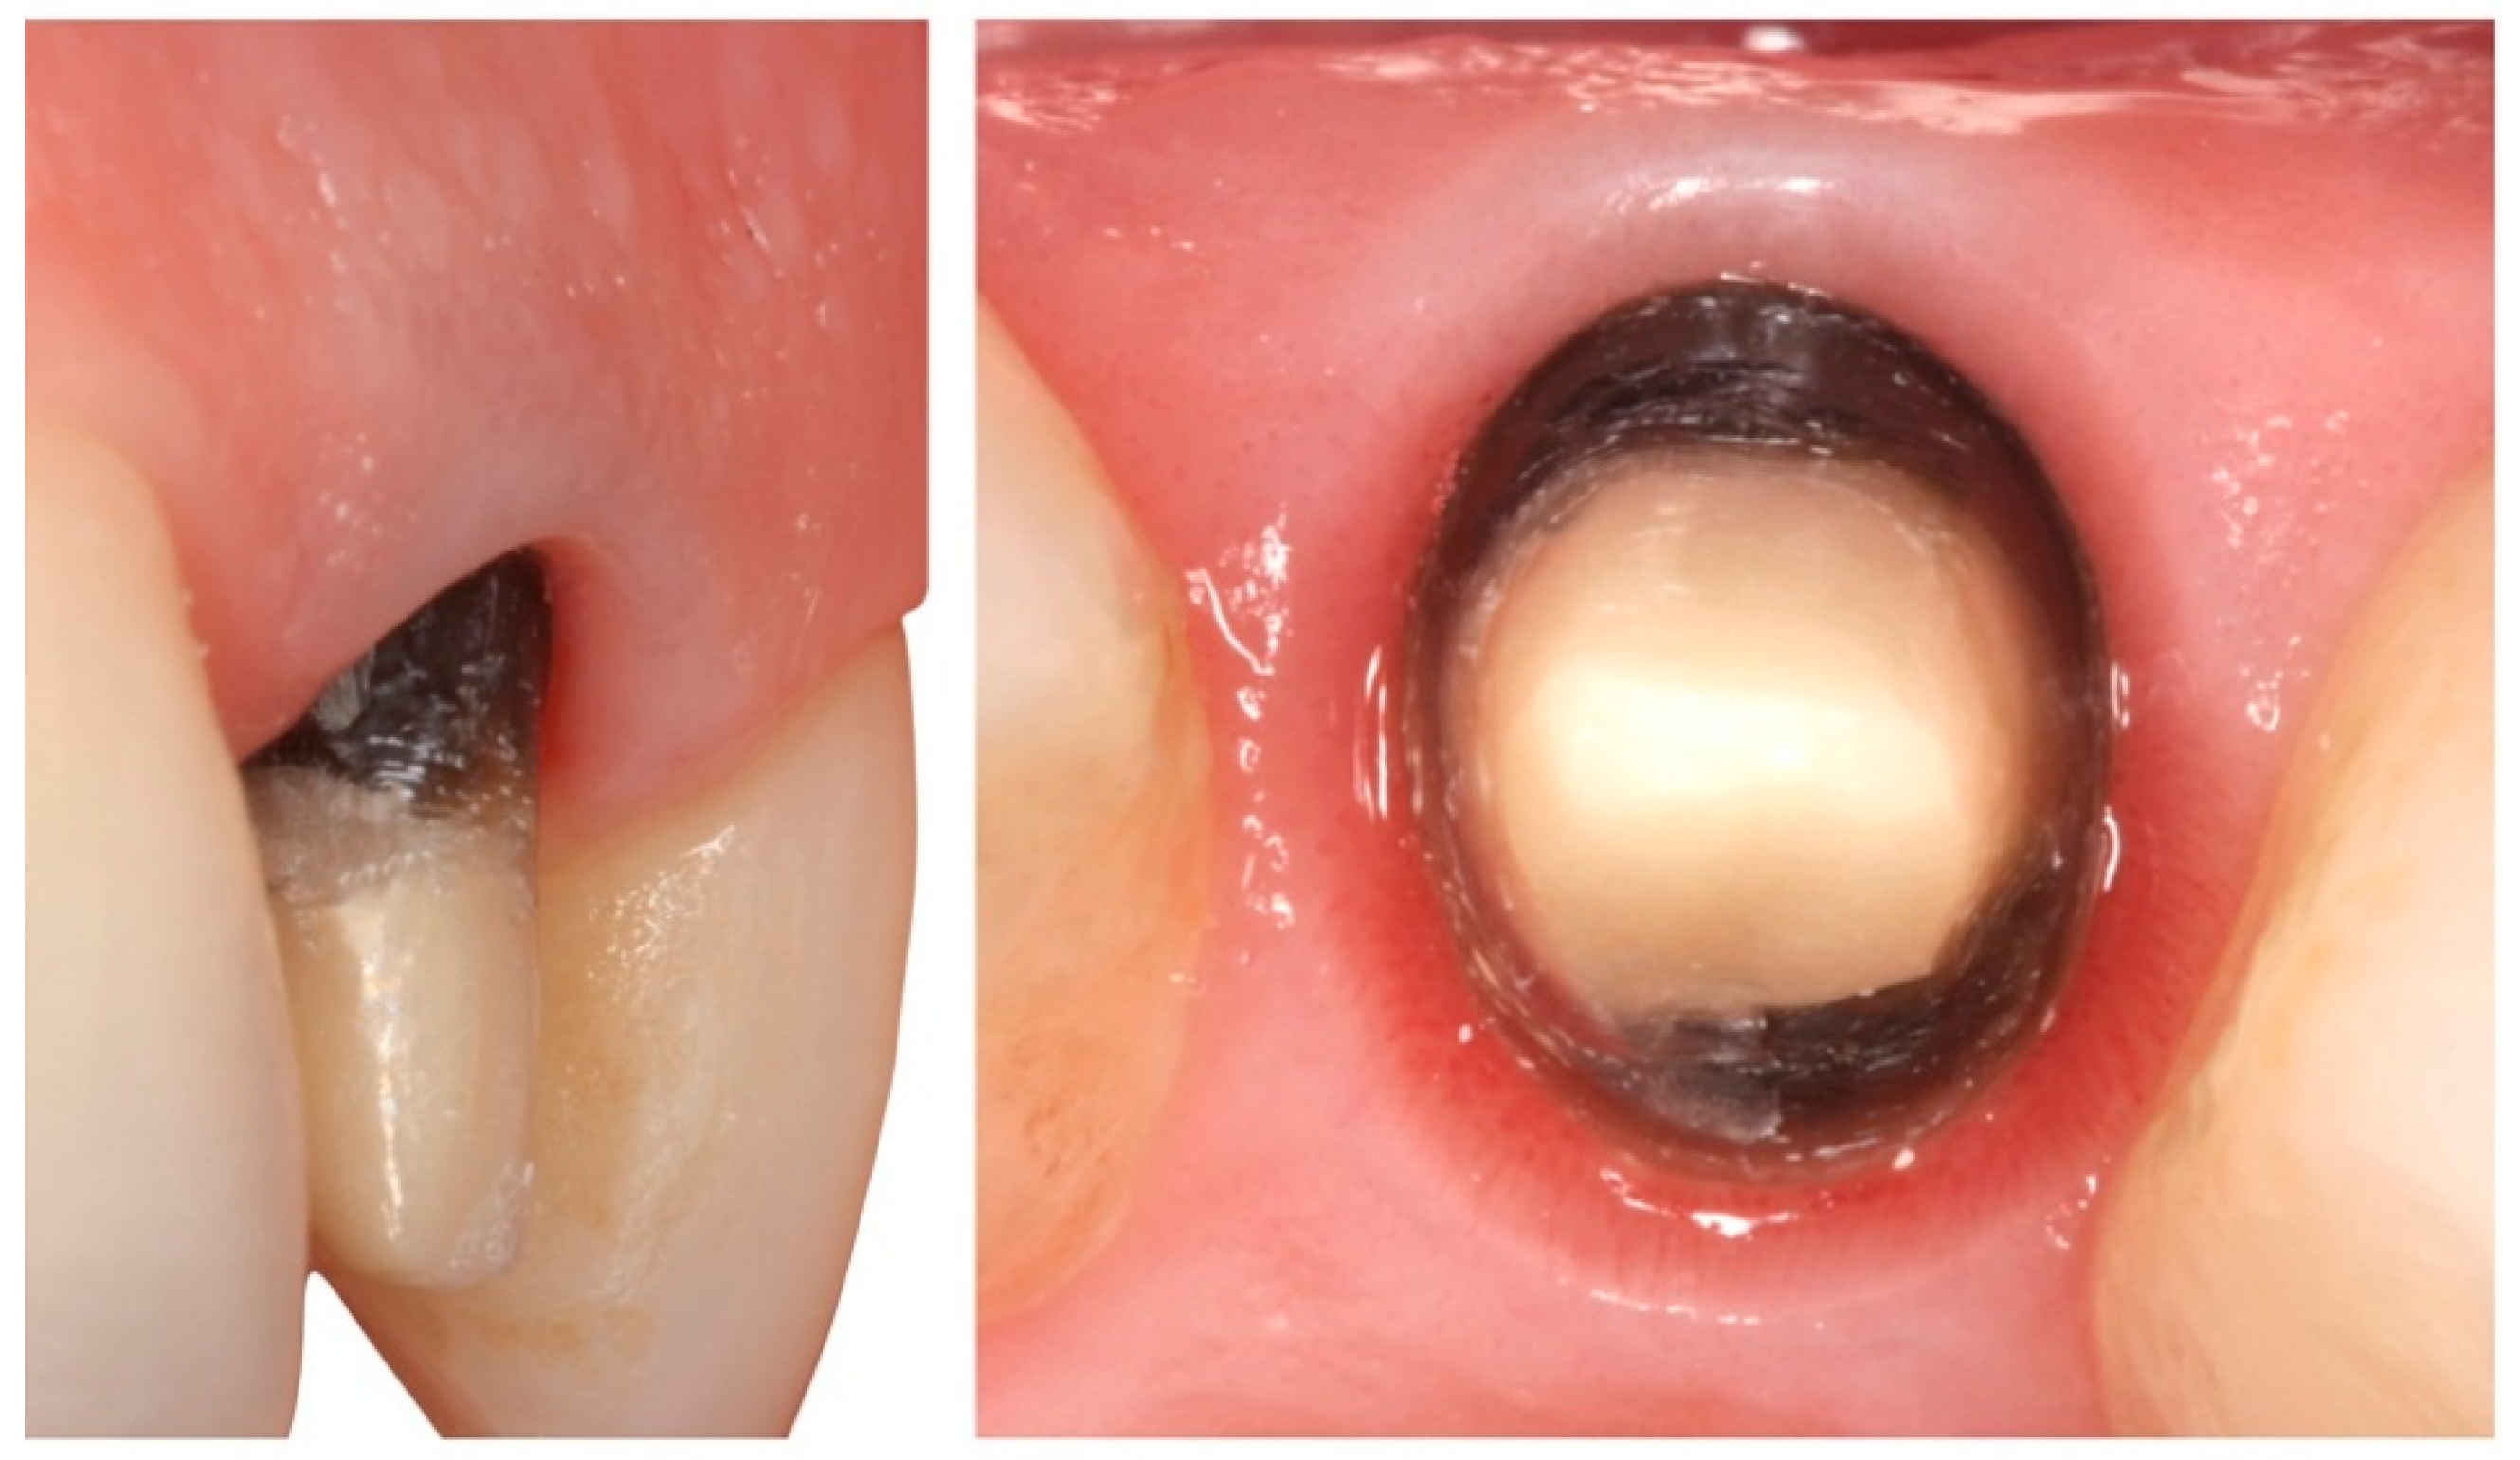

A total of 31 previous restorations were withdrawn (incisives and upper canines), one for each patient, and these teeth were prepared using BOPT (Figure 1 and Figure 2) [6]. The clinical sequence for BOPT was as follows: Before the removal of the old restorations, double probing (gingival sulcus probing and bone probing) was performed to determine the preparation limit and to situate the location of the provisional restoration (0.5–0.8 mm below the edge of the gingiva) so as not to invade the supracrestal attached tissue. After the removal of the old restorations, BOPT preparation eliminated the pre-existing finish line using a turbine and 100/200 μm cone diamond bur with a 1.2 mm diameter (862.534.012, BOPT drills; Sweden and Martina, Due Carrere, Padua, Italy). For realization of the BOPT preparation technique, the bur was first introduced with an angulation of 10–15° with respect to the dental axis. This first step aimed to open the dental groove and eliminate the first millimetre of the emergence of the anatomic crown. In the second step, the bur was introduced parallel to the dental axis in order to eliminate the pre-existing finish line. In the third and final step, the bur was introduced at a 3–6° angle with respect to the dental axis to give it the necessary convergence (Figure 3). Afterwards, in accordance with the protocol guidelines, a provisional crown was made in the clinic for each tooth with self-polymerizing acrylic resin (Sintodent, Sintodent s.r.l., Roma Italy) with an approximate angle of 45°. The provisional prosthesis created a new cement–enamel–prosthetic junction situated in the gingival sulcus at a depth of 0.5–0.8 mm, with consideration of the biological width. Provisional restorations were not removed until the soft tissues had completely matured—a period of 8–12 weeks.

Figure 2. (a) Tooth after restoration being removed, with a chamfer finishing line. (b) Tooth after biologically oriented preparation technique (BOPT) preparation technique.